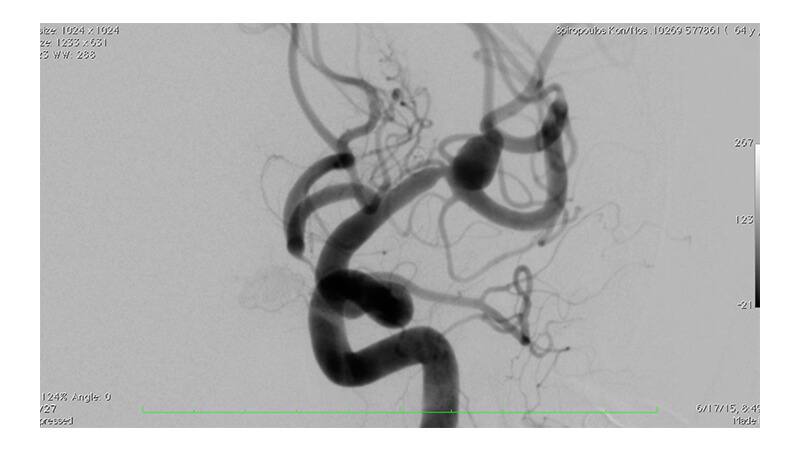

Εικόνα 1: Αγγειογραφία της αριστερής έσω καρωτίδος: Διακρίνεται μη ραγέν ανεύρυσμα του διχασμού της αριστερής μέσης εγκεφαλικής αρτηρίας.

Από την βάση του ανευρυσματικού σάκκου φαίνεται να εκφύεται μετωπιαίος κλάδος. Αμέσως πριν το ανεύρυσμα, στο τελικό Μ1 τμήμα, ελέγχεται τοπική στένωση της μέσης εγκεφαλικής αρτηρίας.